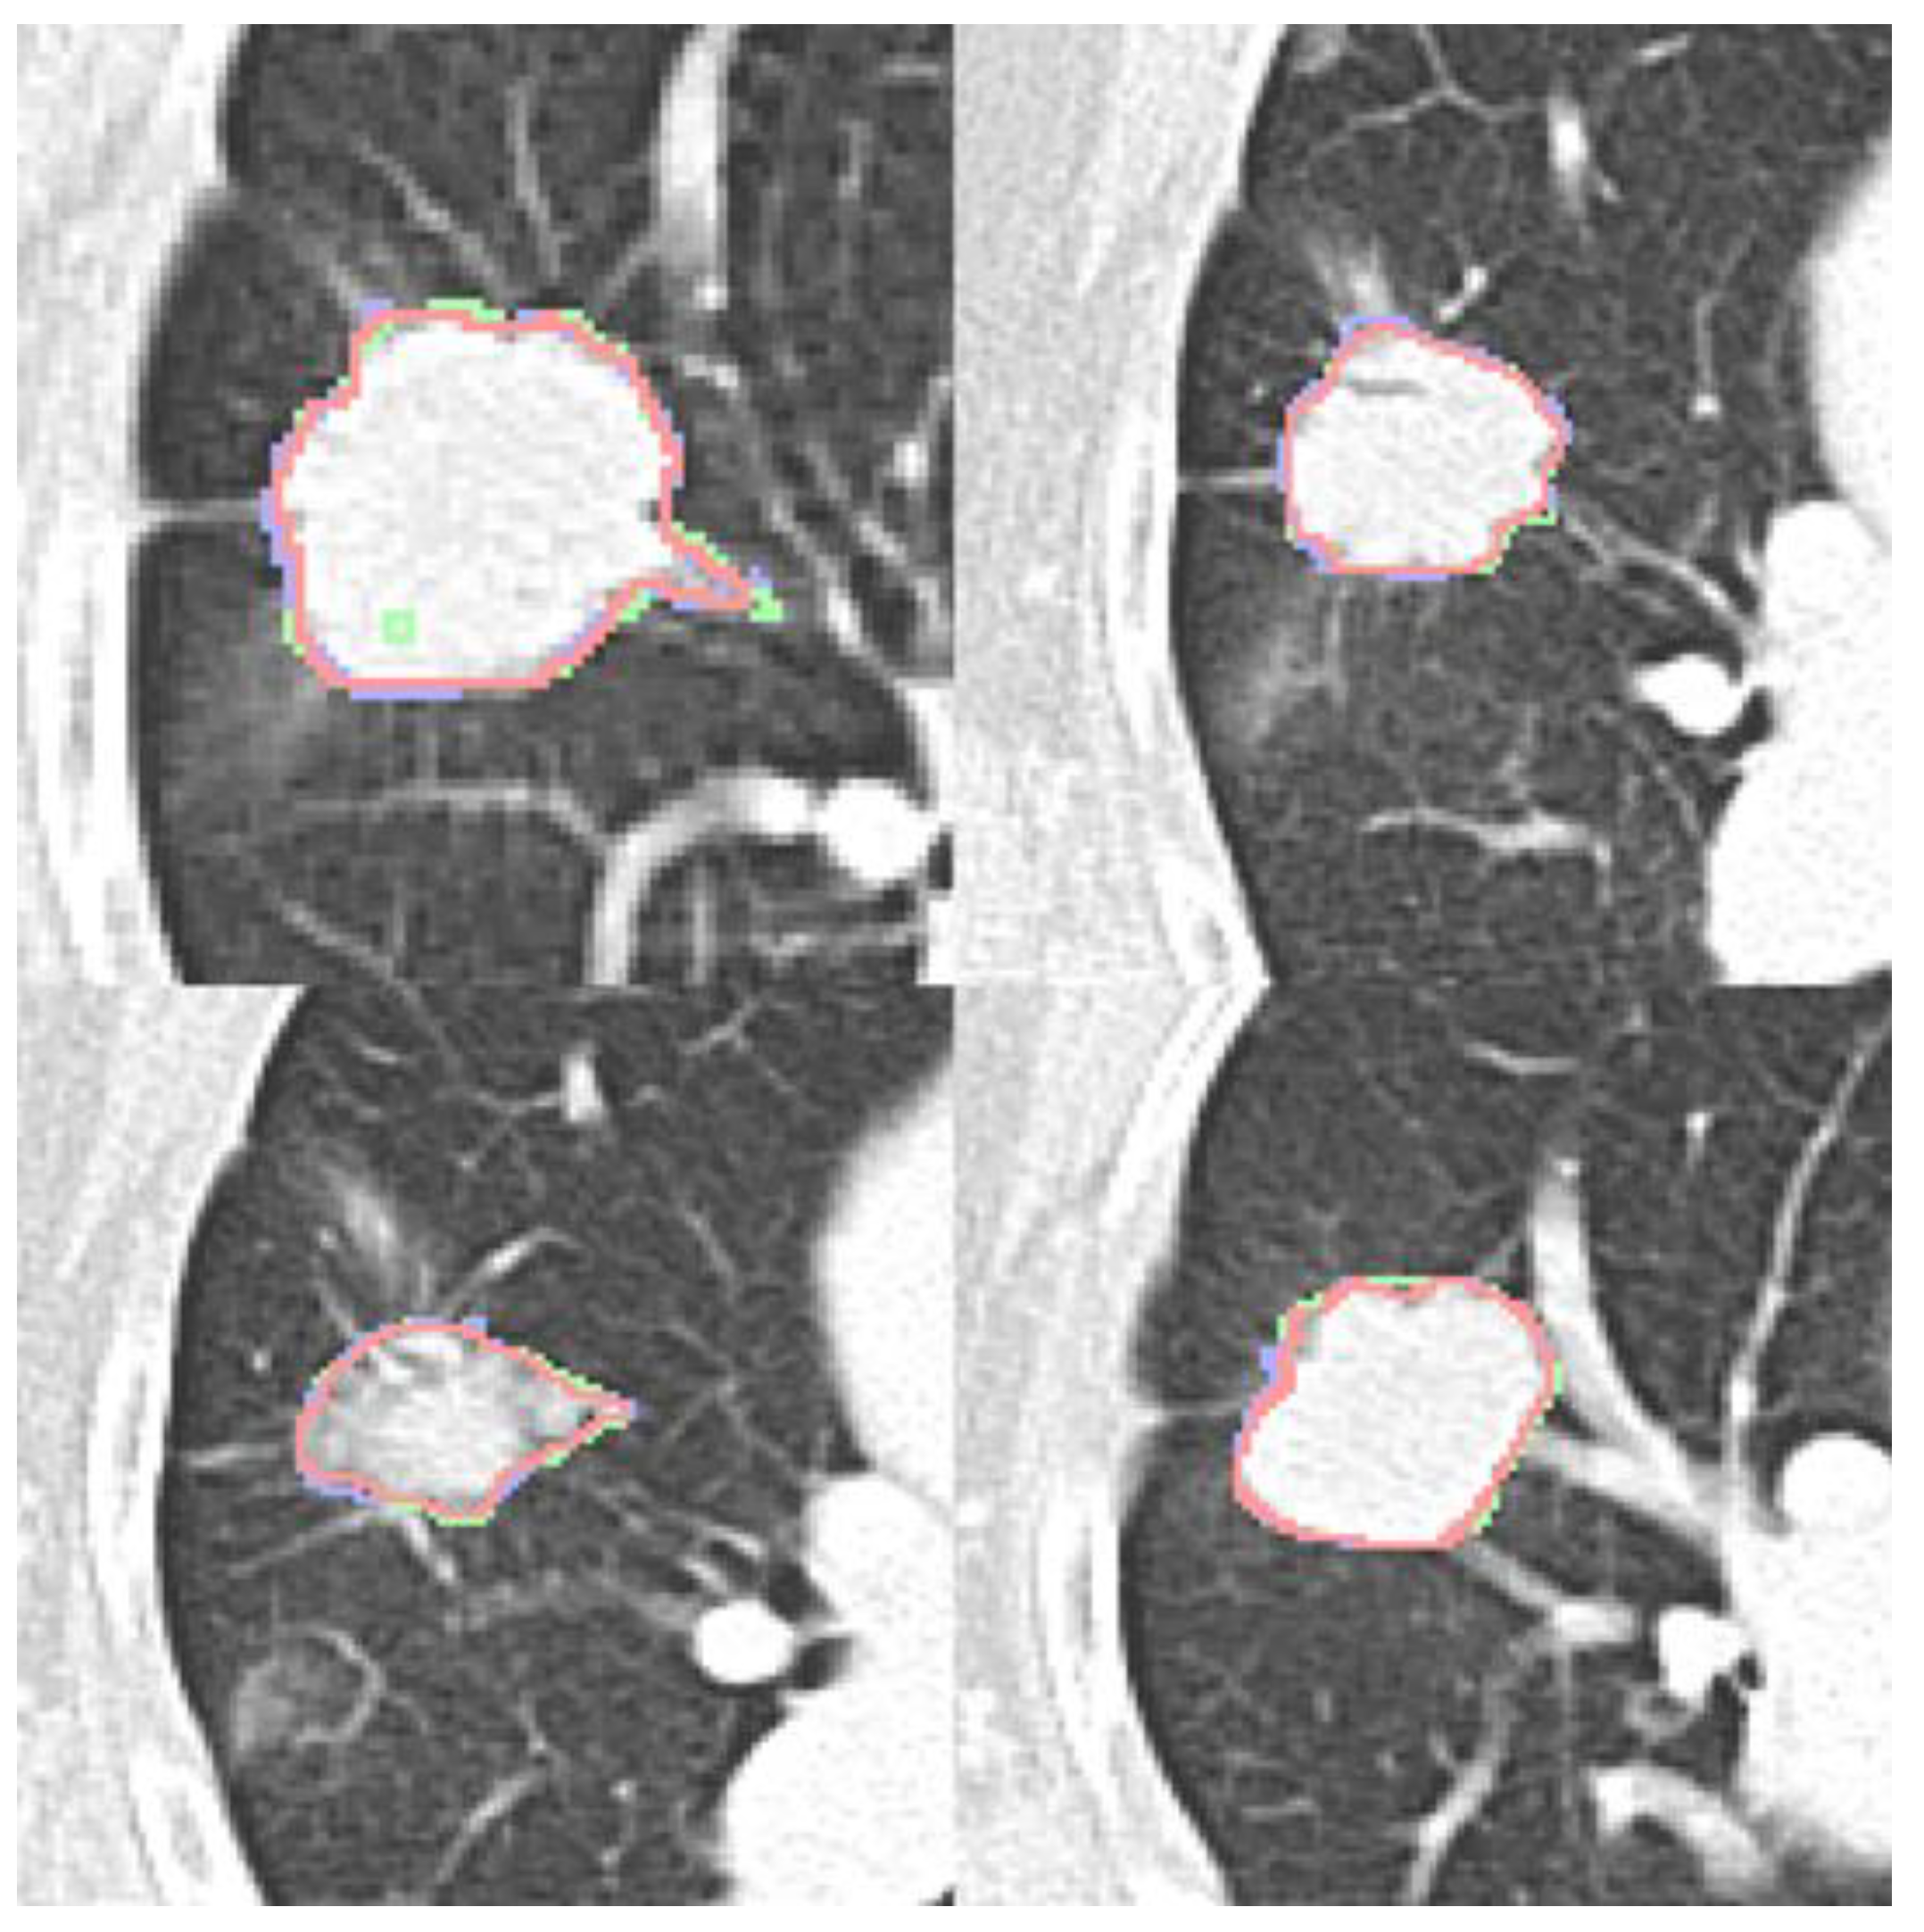

Four expert contours exist in the LIDC-IDRI dataset and two in the dataset (b). Four qualitative contour fusion results are demonstrated in Figure 3. Three contours are superimposed on the raw patch. The blue and green colors represent two manual contours, while the red color indicates the fusion result. Minor inconsistencies are observable. Notably, there is a manual error in Fig. 3(a), represented in green, where an extra point is erroneously included. However, the fusion result does not reflect this mistake. The proposed contour fusion technique effectively mitigates sharp variations exhibited by both experts, such as protrusions or indentations, thereby addressing the gaps left by incomplete annotations.

Figure 3. : Four contour fusion results. Three contours are superimposed on a raw patch. The blue and green lines illustrate contours meticulously delineated by two human experts. The red line represents the contour fusion, which aligns the nodule areas from the two experts, providing a refined depiction.